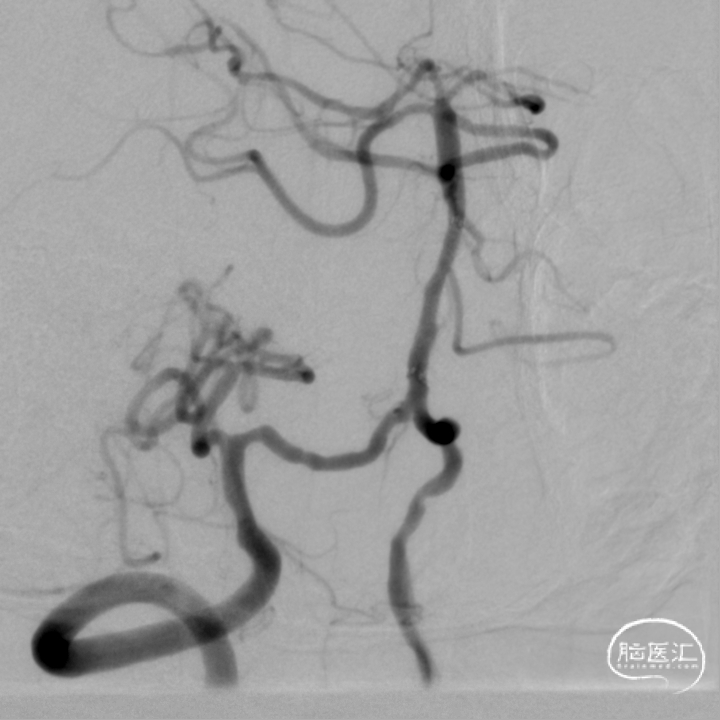

术前DSA影像:

右侧桡动脉穿刺置动脉鞘,泥鳅导丝配合6F 115cm Valent®颅内支撑导管内嵌行至右侧锁骨下动脉近右侧椎动脉起始段处,将导丝配合中间导管上行至椎动脉V3段,撤出泥鳅导丝,手推造影,显示:基底动脉中段可见重度狭窄,狭窄率约80%。

将微导丝头端置右侧大脑后动脉,沿微导丝引入2.0*10mm球囊,小心扩张狭窄段,撤出球囊后造影,原有狭窄较前稍好转,沿微导丝引入支架用微导管置于基底动脉,撤出微导丝,保留微导管,沿微导管引入3.5*15mm Neuroform EZ支架,缓慢释放,复查造影,狭窄较前明显好转,支架贴壁良好。